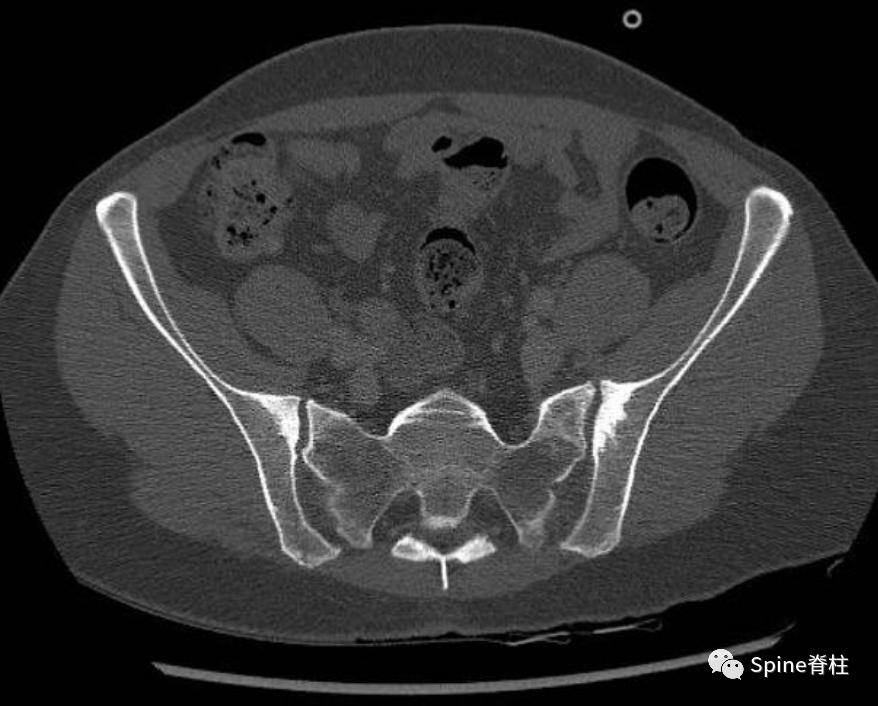

CT提示主要发生在靠近两个骶髂关节的髂骨侧骨硬化,未观察到关节不规则、侵蚀或关节间隙变窄

上述同一个病例,MRI也提示骶髂关节髂骨侧硬化 (下图)。